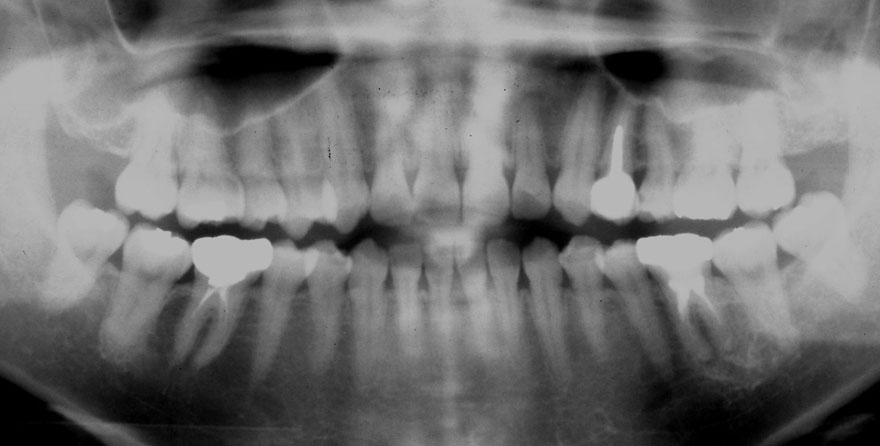

初診時 39歳 女性 平均歯槽骨喪失量:1.82mm

29年後 68歳

平均歯槽骨喪失量:2.21mm

29年間喪失量:-0.39mm

年間喪失速度:-0.013mm

(ケア頻度:5.55ヵ月ごと)